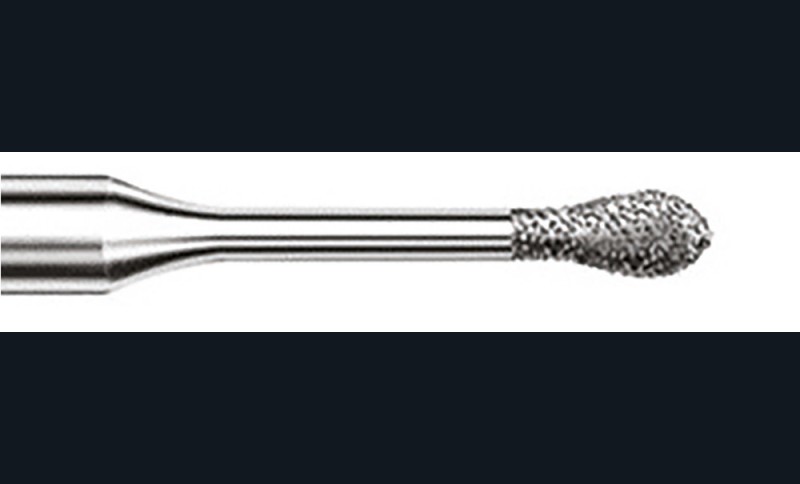

- soit de façon invasive a minima. Cette économie tissulaire peut se faire notamment avec l’utilisation de fraises adaptées et minimalement invasives (fig. 4).

• Traitement invasif a minima : il concerne les lésions carieuses cavitaires ou non avec atteinte dentinaire (à partir du 1/3 moyen dentinaire), soit ICDAS 3 à 6. Dans ce cas, la priorité est de préserver la dent d’une effraction pulpaire éventuelle (recommandations de l’ESE) [4]. C’est pourquoi, lors du traitement de lésions carieuses profondes (ICDAS 4 à 6), il faut dans tous les cas réaliser une éviction sélective, réaliser une préparation a minima (favoriser les préparations de type fente (« slot ») ou tunnel lorsque l’indication se pose) et utiliser un matériau de restauration de choix, soit composite, soit un ciment verre ionomère (CVI), soit des matériaux à base de silicate de calcium ou encore les nouveaux composites enrichis en minéraux (fig. 7 à 9). Ces préparations a minima peuvent être réalisées avec des fraises de petits diamètres (fig. 10 et 11).